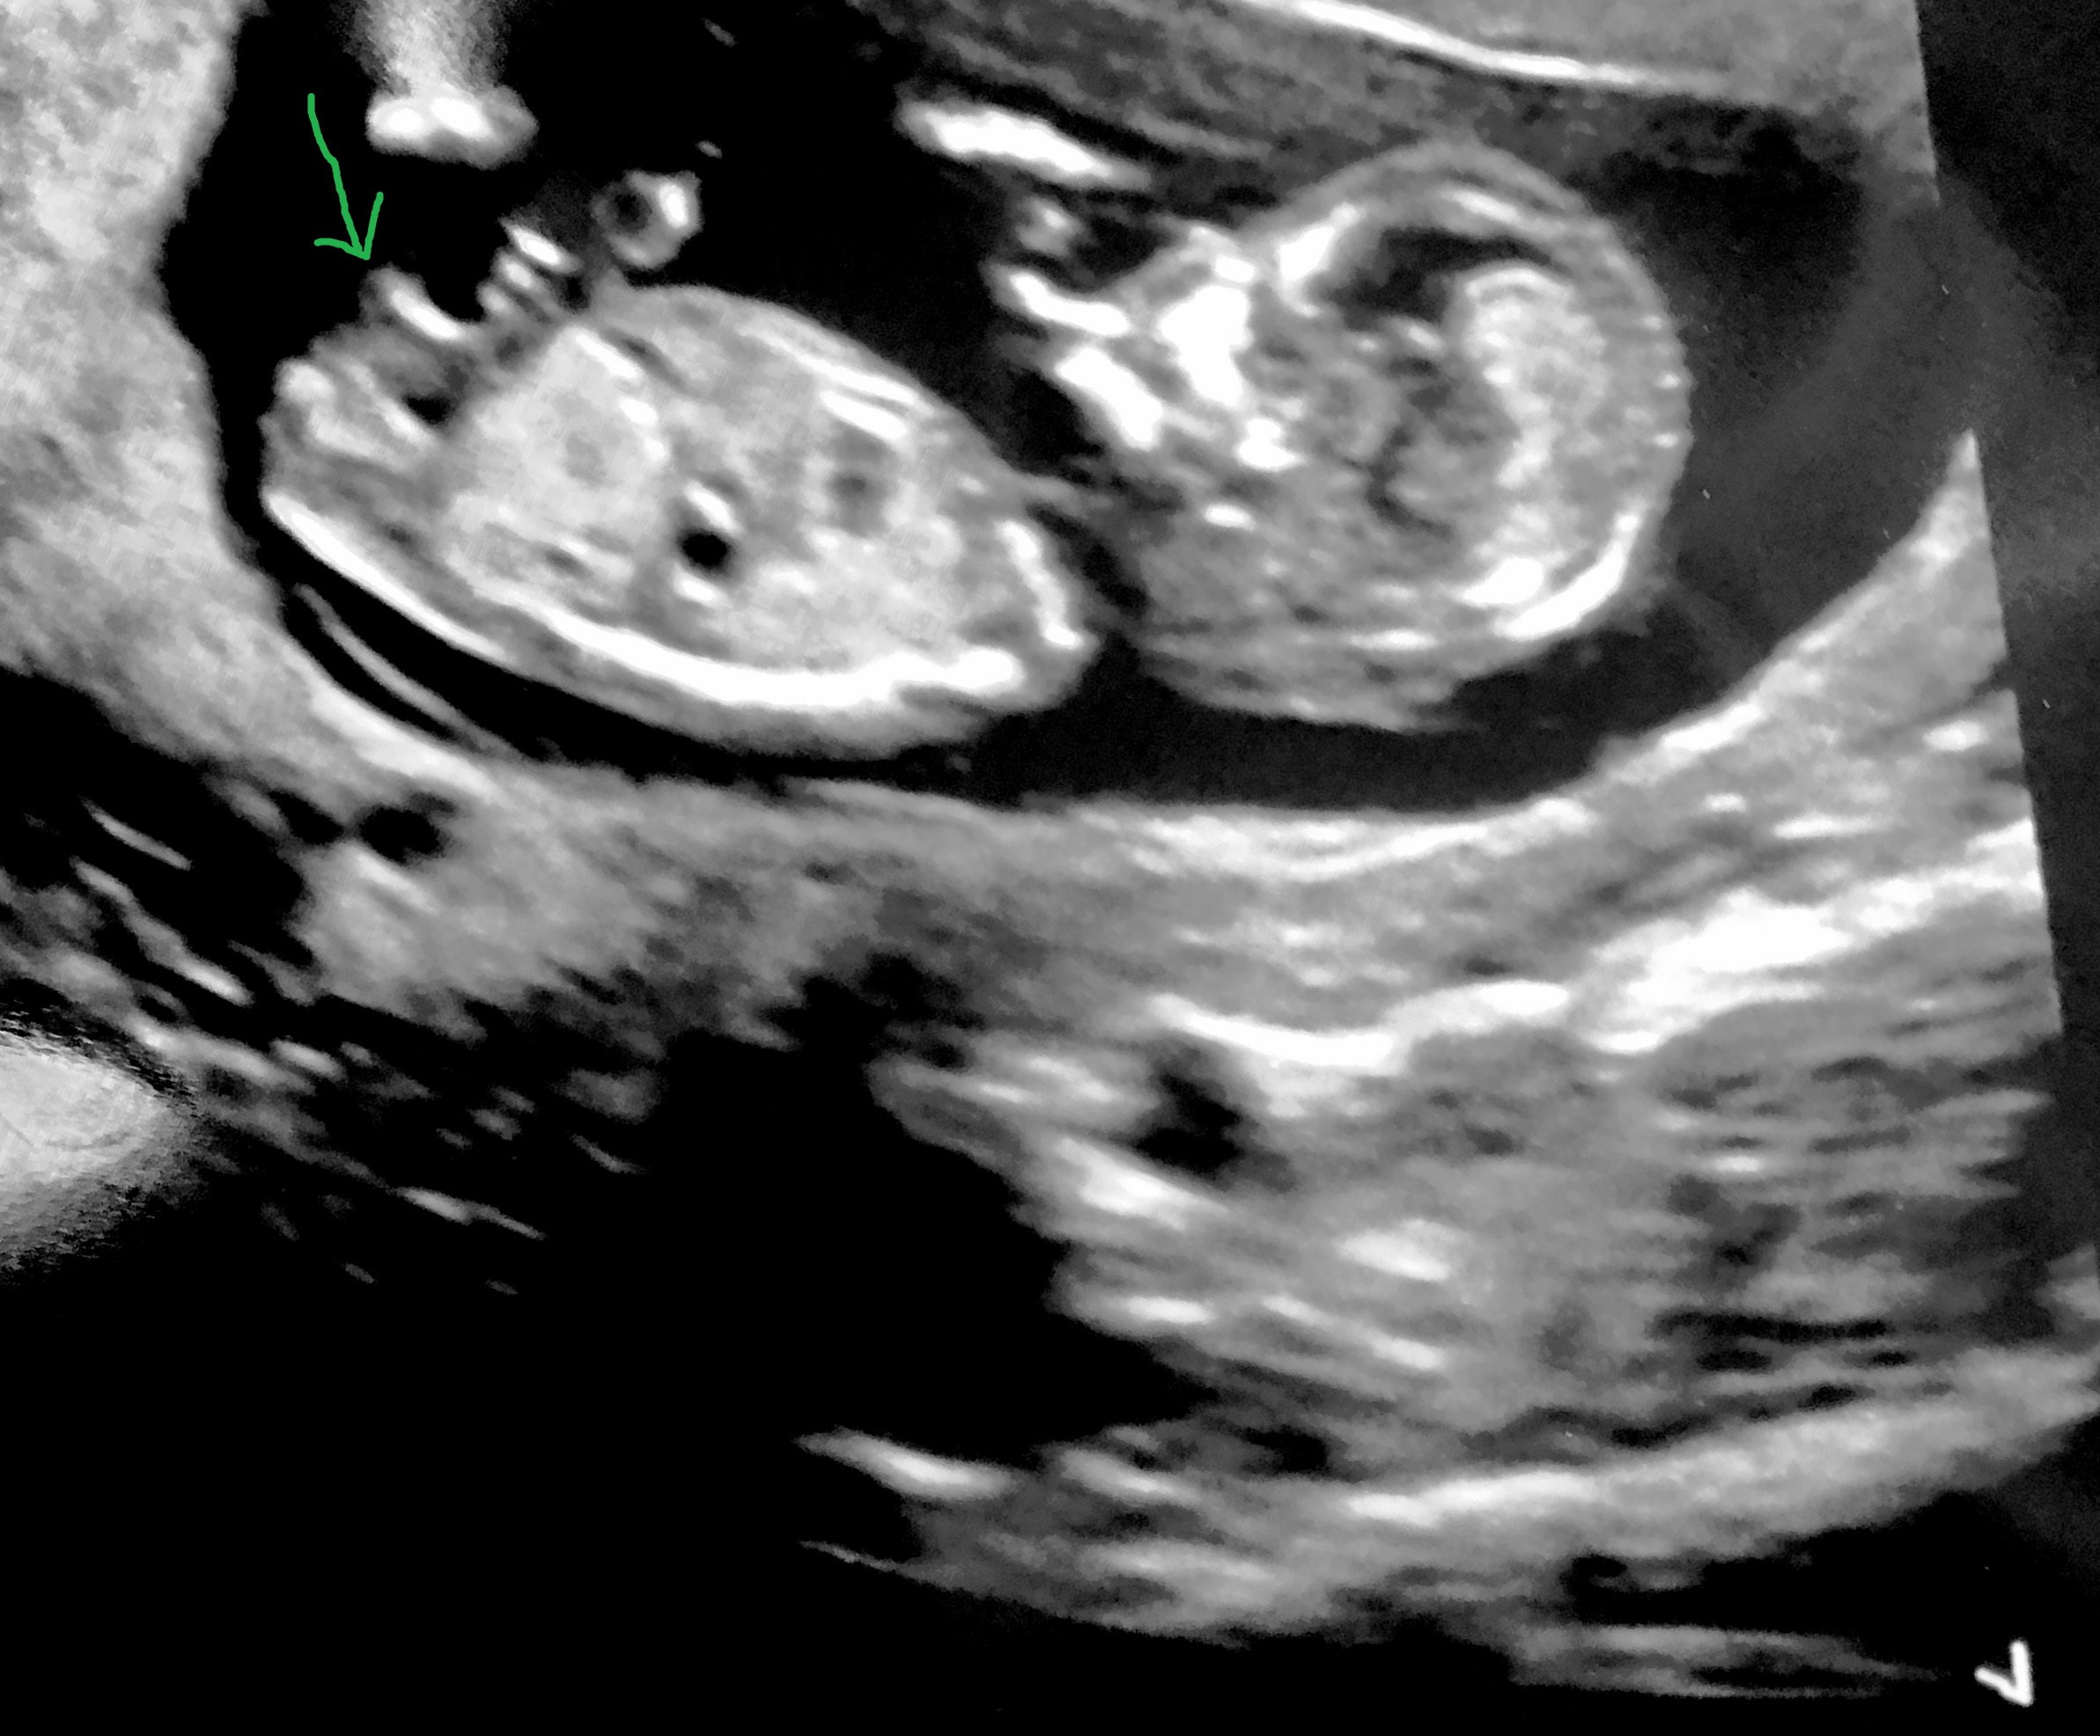

Attachment 34745

I wondered if that isn't the nub and above my arrow you can see one?

These make me think girl

Slight girl lean xx

So the forked thing just below what is the nub is prob a leg or something? Sorry I'm not great at this lol